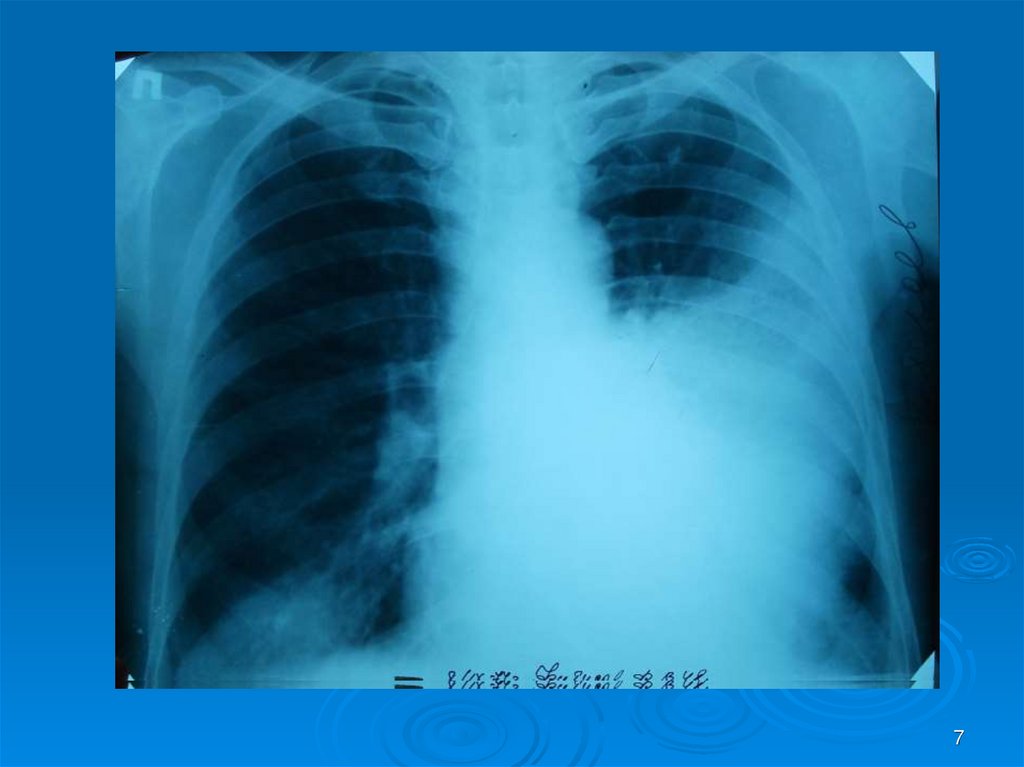

7.

7